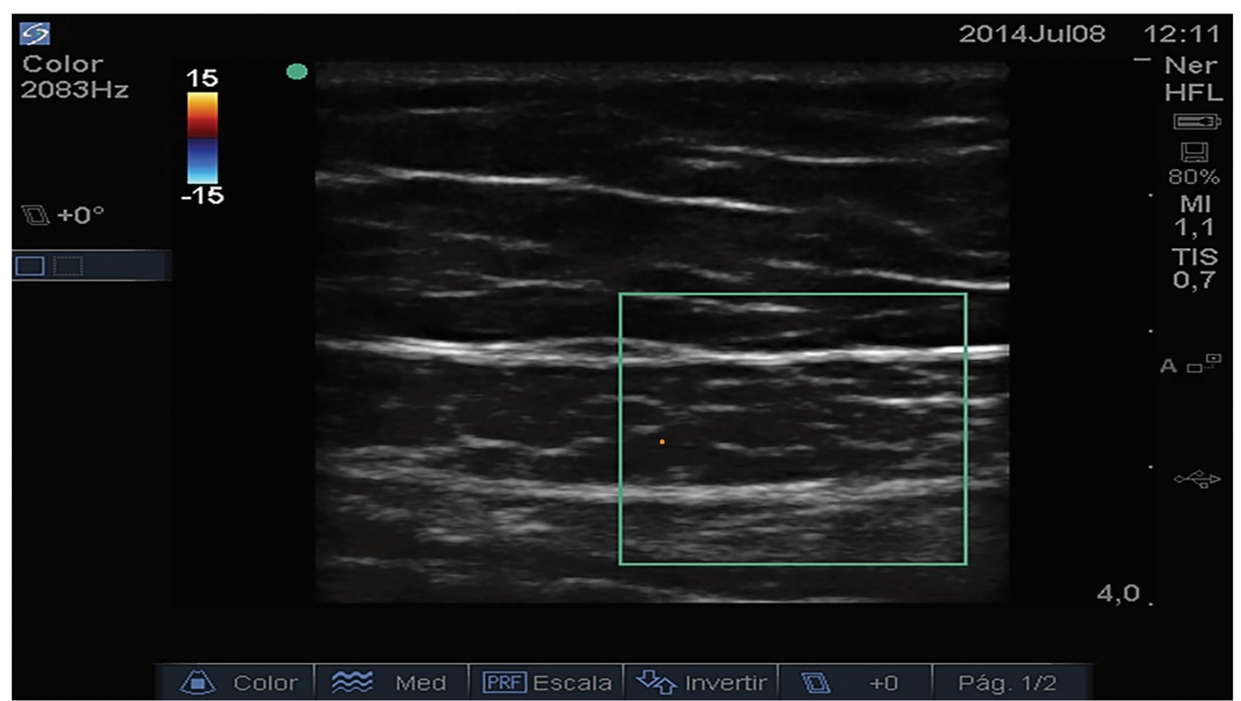

Ramas de la arteria epigástrica inferior (que trascurre caudocefálico en el plano entre la hoja posterior de la fascia y el músculo recto abdominal) perforan e irrigan el músculo recto y pueden verse con las aplicaciones Doppler color y Power Doppler [4,11]. La variabilidad anatómica de las arterias epigástricas y sus ramas musculares hacen aconsejable el uso de ultrasonido para su identificación y consecuente disminución de la frecuencia de hematomas asociados al bloqueo [2].

El paciente debe estar en posición supina con la pared abdominal anterior descubierta. La piel, el transductor y los equipos deben ser preparados de forma estéril. Se debe usar un transductor lineal de alta frecuencia para obtener un corte transversal (alternativamente sagital) del músculo recto abdominal a nivel del ombligo (lateral a este) y mejorar las características para obtener la mejor imagen posible (frecuencia, profundidad, foco y ganancia) (figura 1). Se aconseja utilizar las aplicaciones Doppler para identificar los vasos epigástricos (figura 2) y evitarlos en la trayectoria planeada de la aguja e identificar el peritoneo la grasa peritoneal y las vísceras debajo del peritoneo (movimientos peristálticos) para evitar punciones peritoneales [13,14]. Los nervios intercostales y sus ramas terminales no son fácilmente identificables, por lo que no son el objetivo primario de la infiltración.